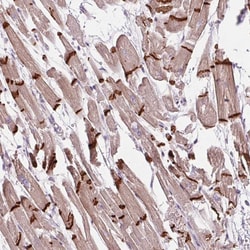

Catenins are proteins that connect cadherin/beta-catenin cell adhesion complexes to the actin cytoskeleton. Although originally discovered in testis, alphaT-catenin is expressed in other tissues, the highest levels being observed in heart. Immunohistochemical analysis showed human alphaTcatenin localization at intercalated discs of cardiomyocytes and in peritubular myoid cells of testis. It is proven that alphaT-catenin can functionally restore cell-cell adhesion in colon cancer cells lacking alpha-catenins. This indicates that this protein is involved in the formation of specific cell-cell contacts in specific types of muscle cells. The encoded protein has about the same predicted size (100 kDa) as other alpha-catenins to which it shows an overall amino acid identity of 57%. In cells transfected with alphaT-catenin cDNA, interaction with alpha-catenin was demonstrated by coimmunoprecipitation. The 892_24D2S antibody against alphaT-catenin does not show any cross reaction with alphaE-catenin or alphaNcatenin in western blot analysis.

| Immunohistochemistry (Paraffin) | |